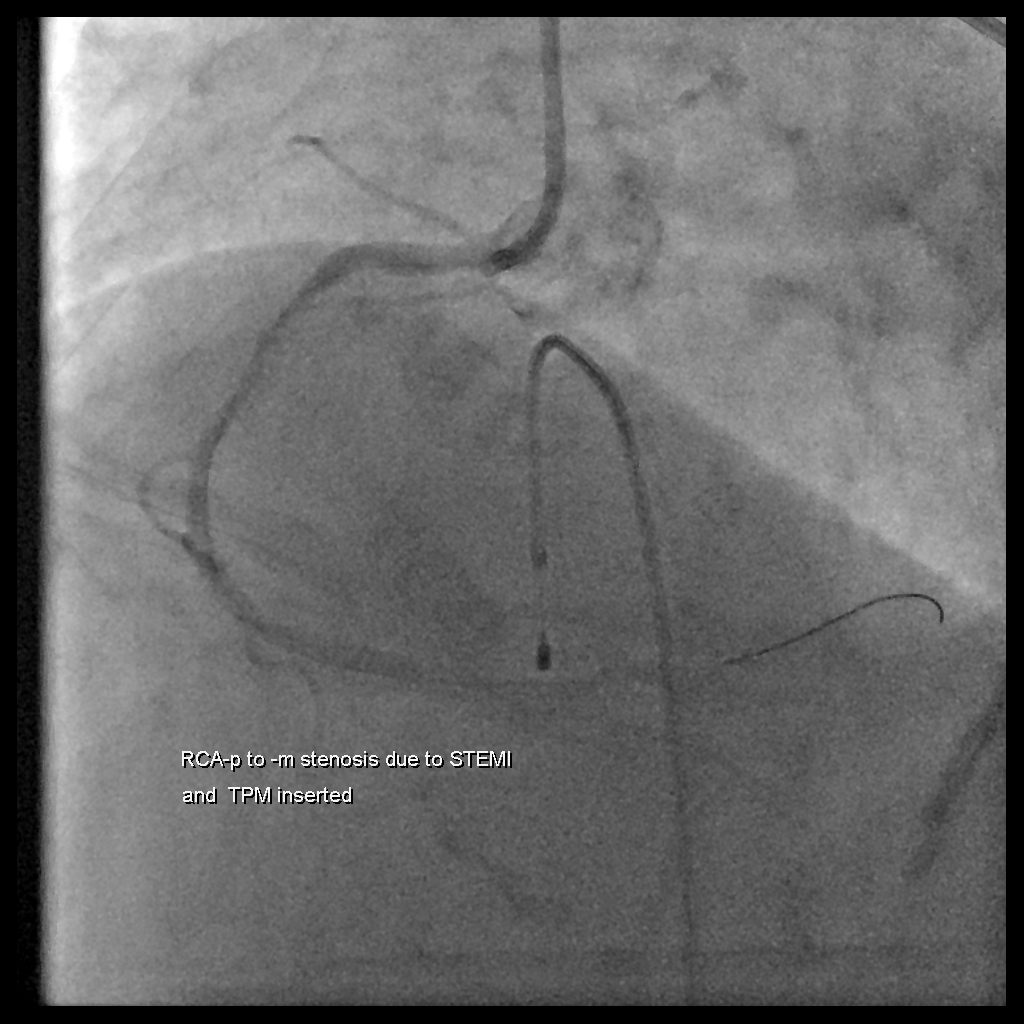

病患後續做了導管

CAG report:Acute STEMI (IRA: RCA) with cardiogenic shock and bradycardia, CAD with 1-vessel disease (RCA-M: 100% acute total occlusion) s/p primary PCI with BMS*1 (Meril NEXGEN 2.75X32mm) over RCA-P to -M